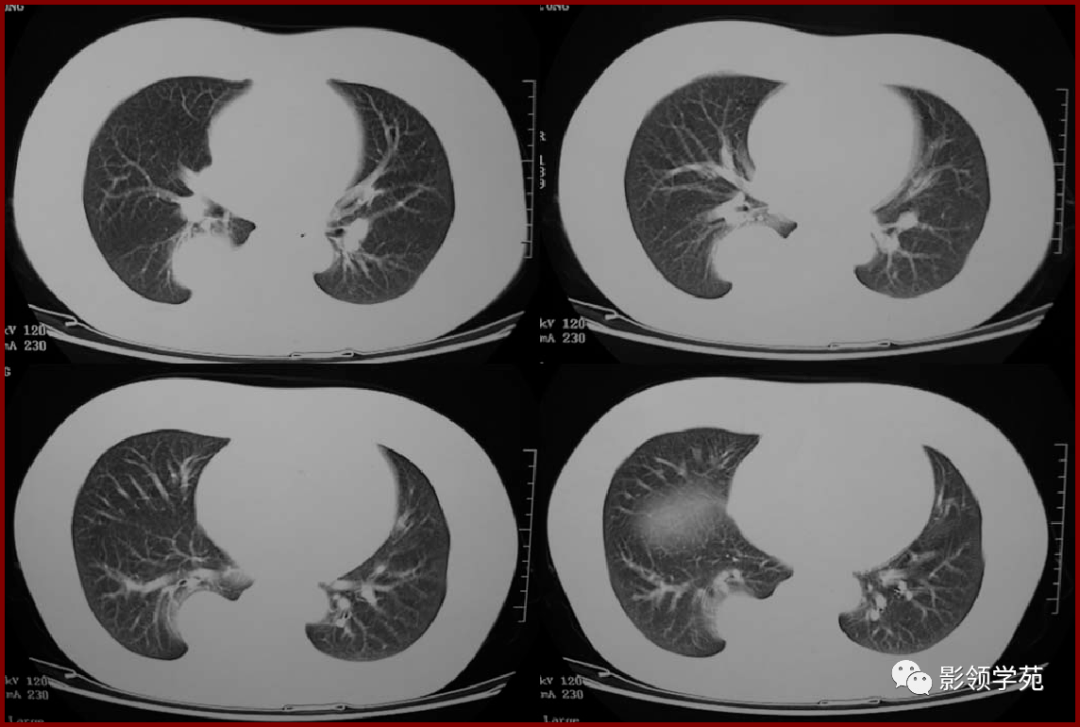

刘懿博士说肺癌二五九〇切之前知道俩肺结节是良性但不是一种病